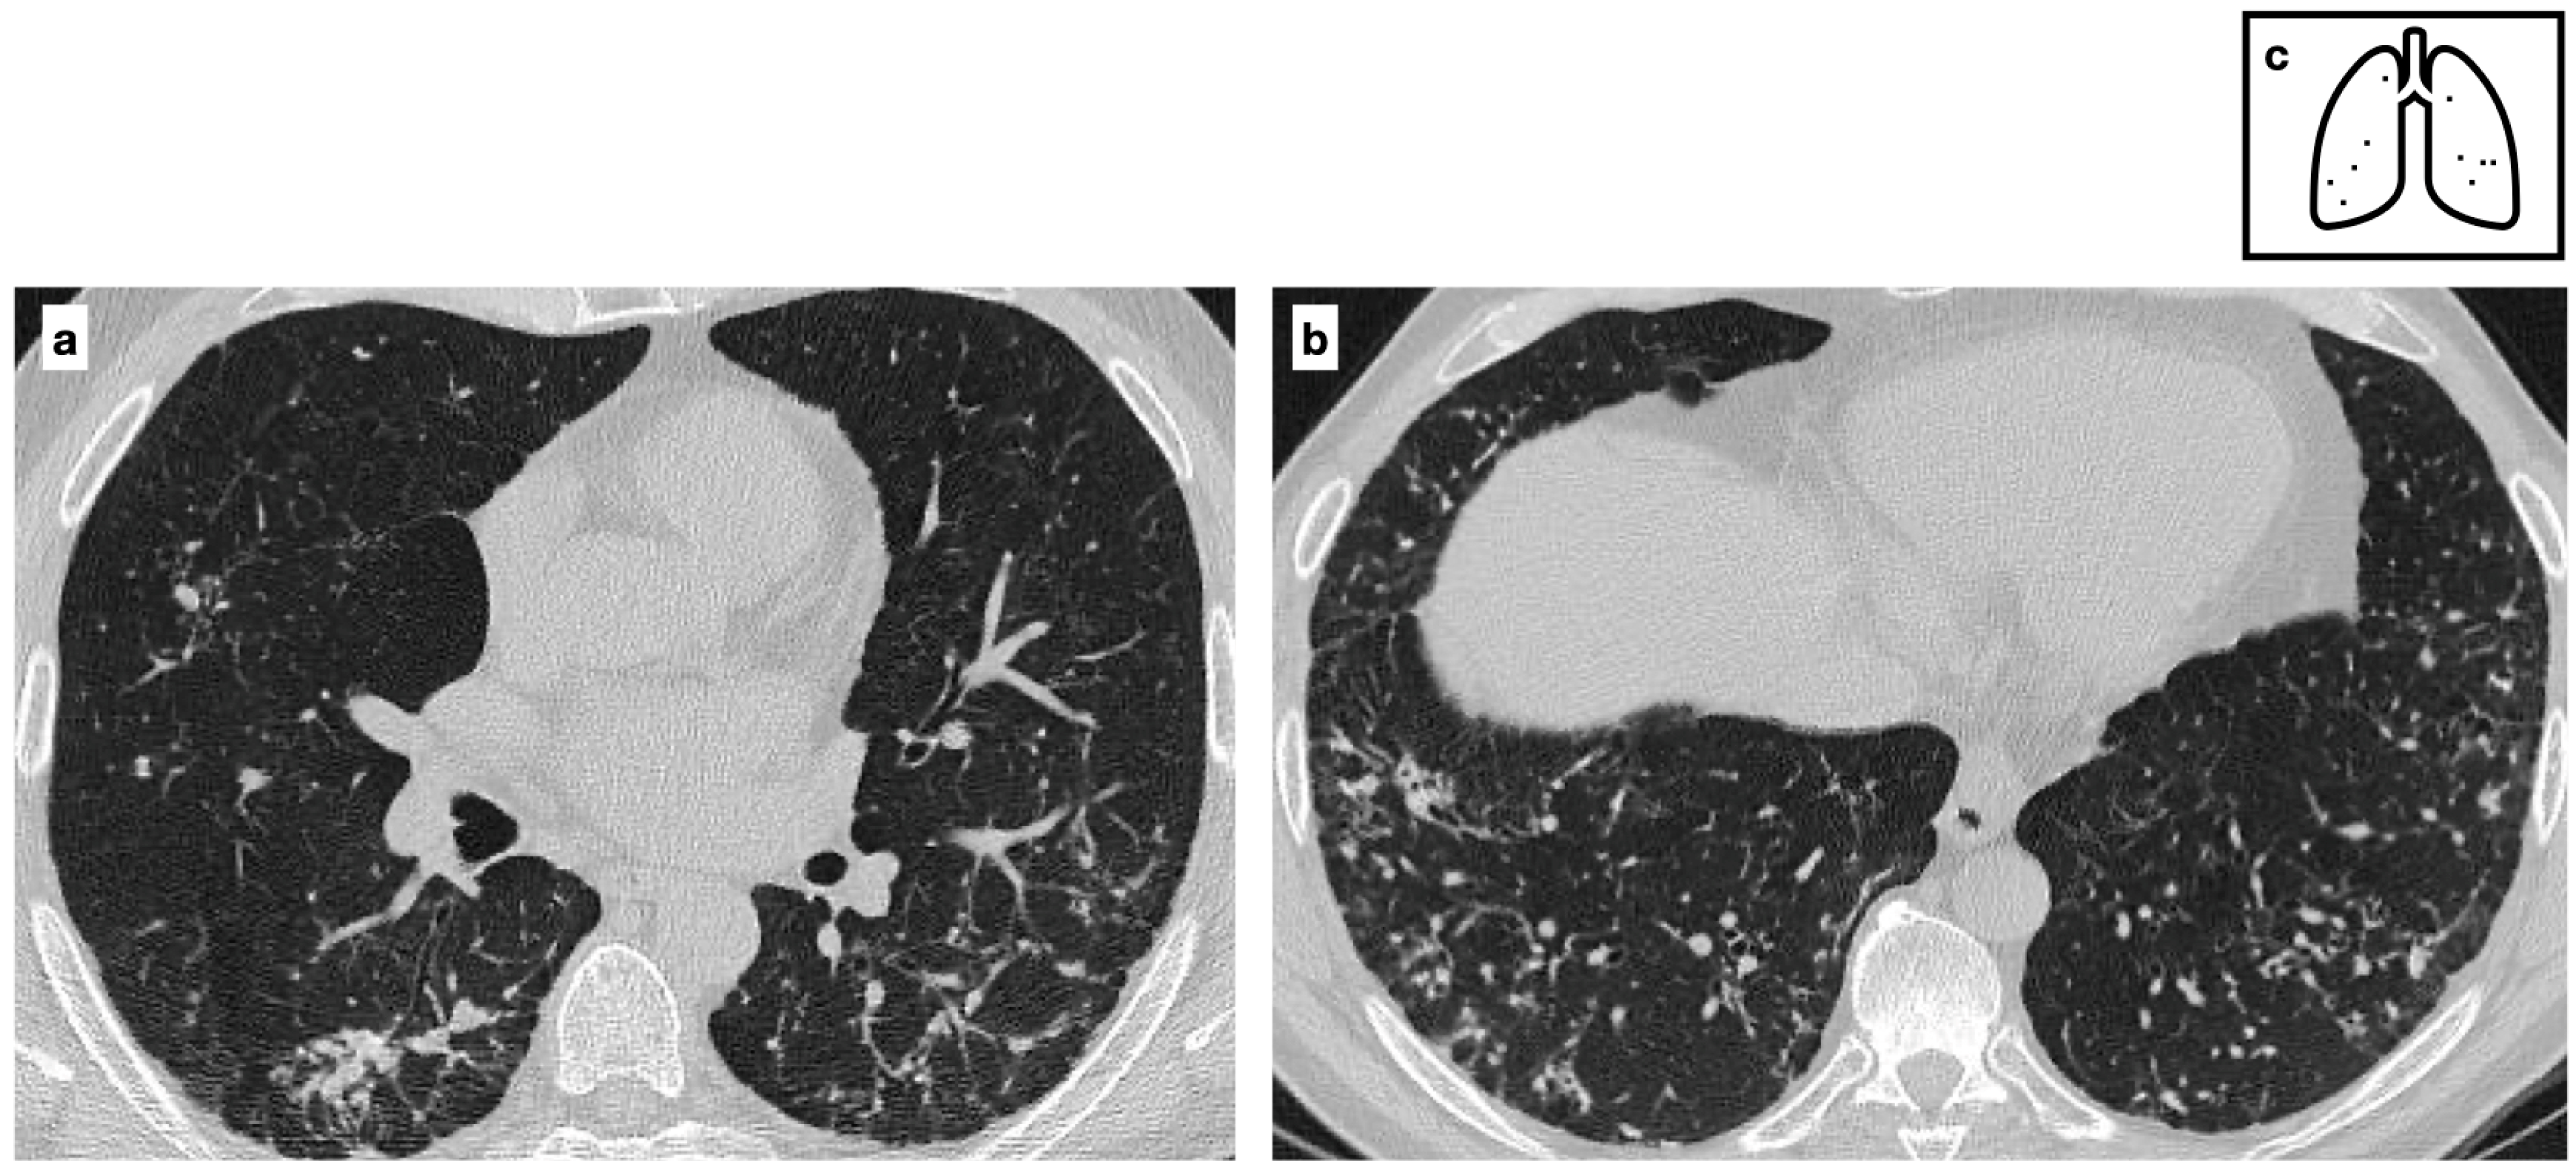

Figure 9.

CT axial images demonstrate a peripheric lung nodule characterized by spiculated margins, small cavitation and an eccentric calcification; this lesion was a biopsy-proven adenocarcinoma (a,b). Heavy smoker patient with severe confluent centrilobular emphysema. HRCT shows a malignant nodule with a small eccentric calcification in the right upper lobe (c). A spiculated nodule with a relatively fast growth rate must always raise the concern for lung cancer in patients with smoking history. Pattern of calcification (d).